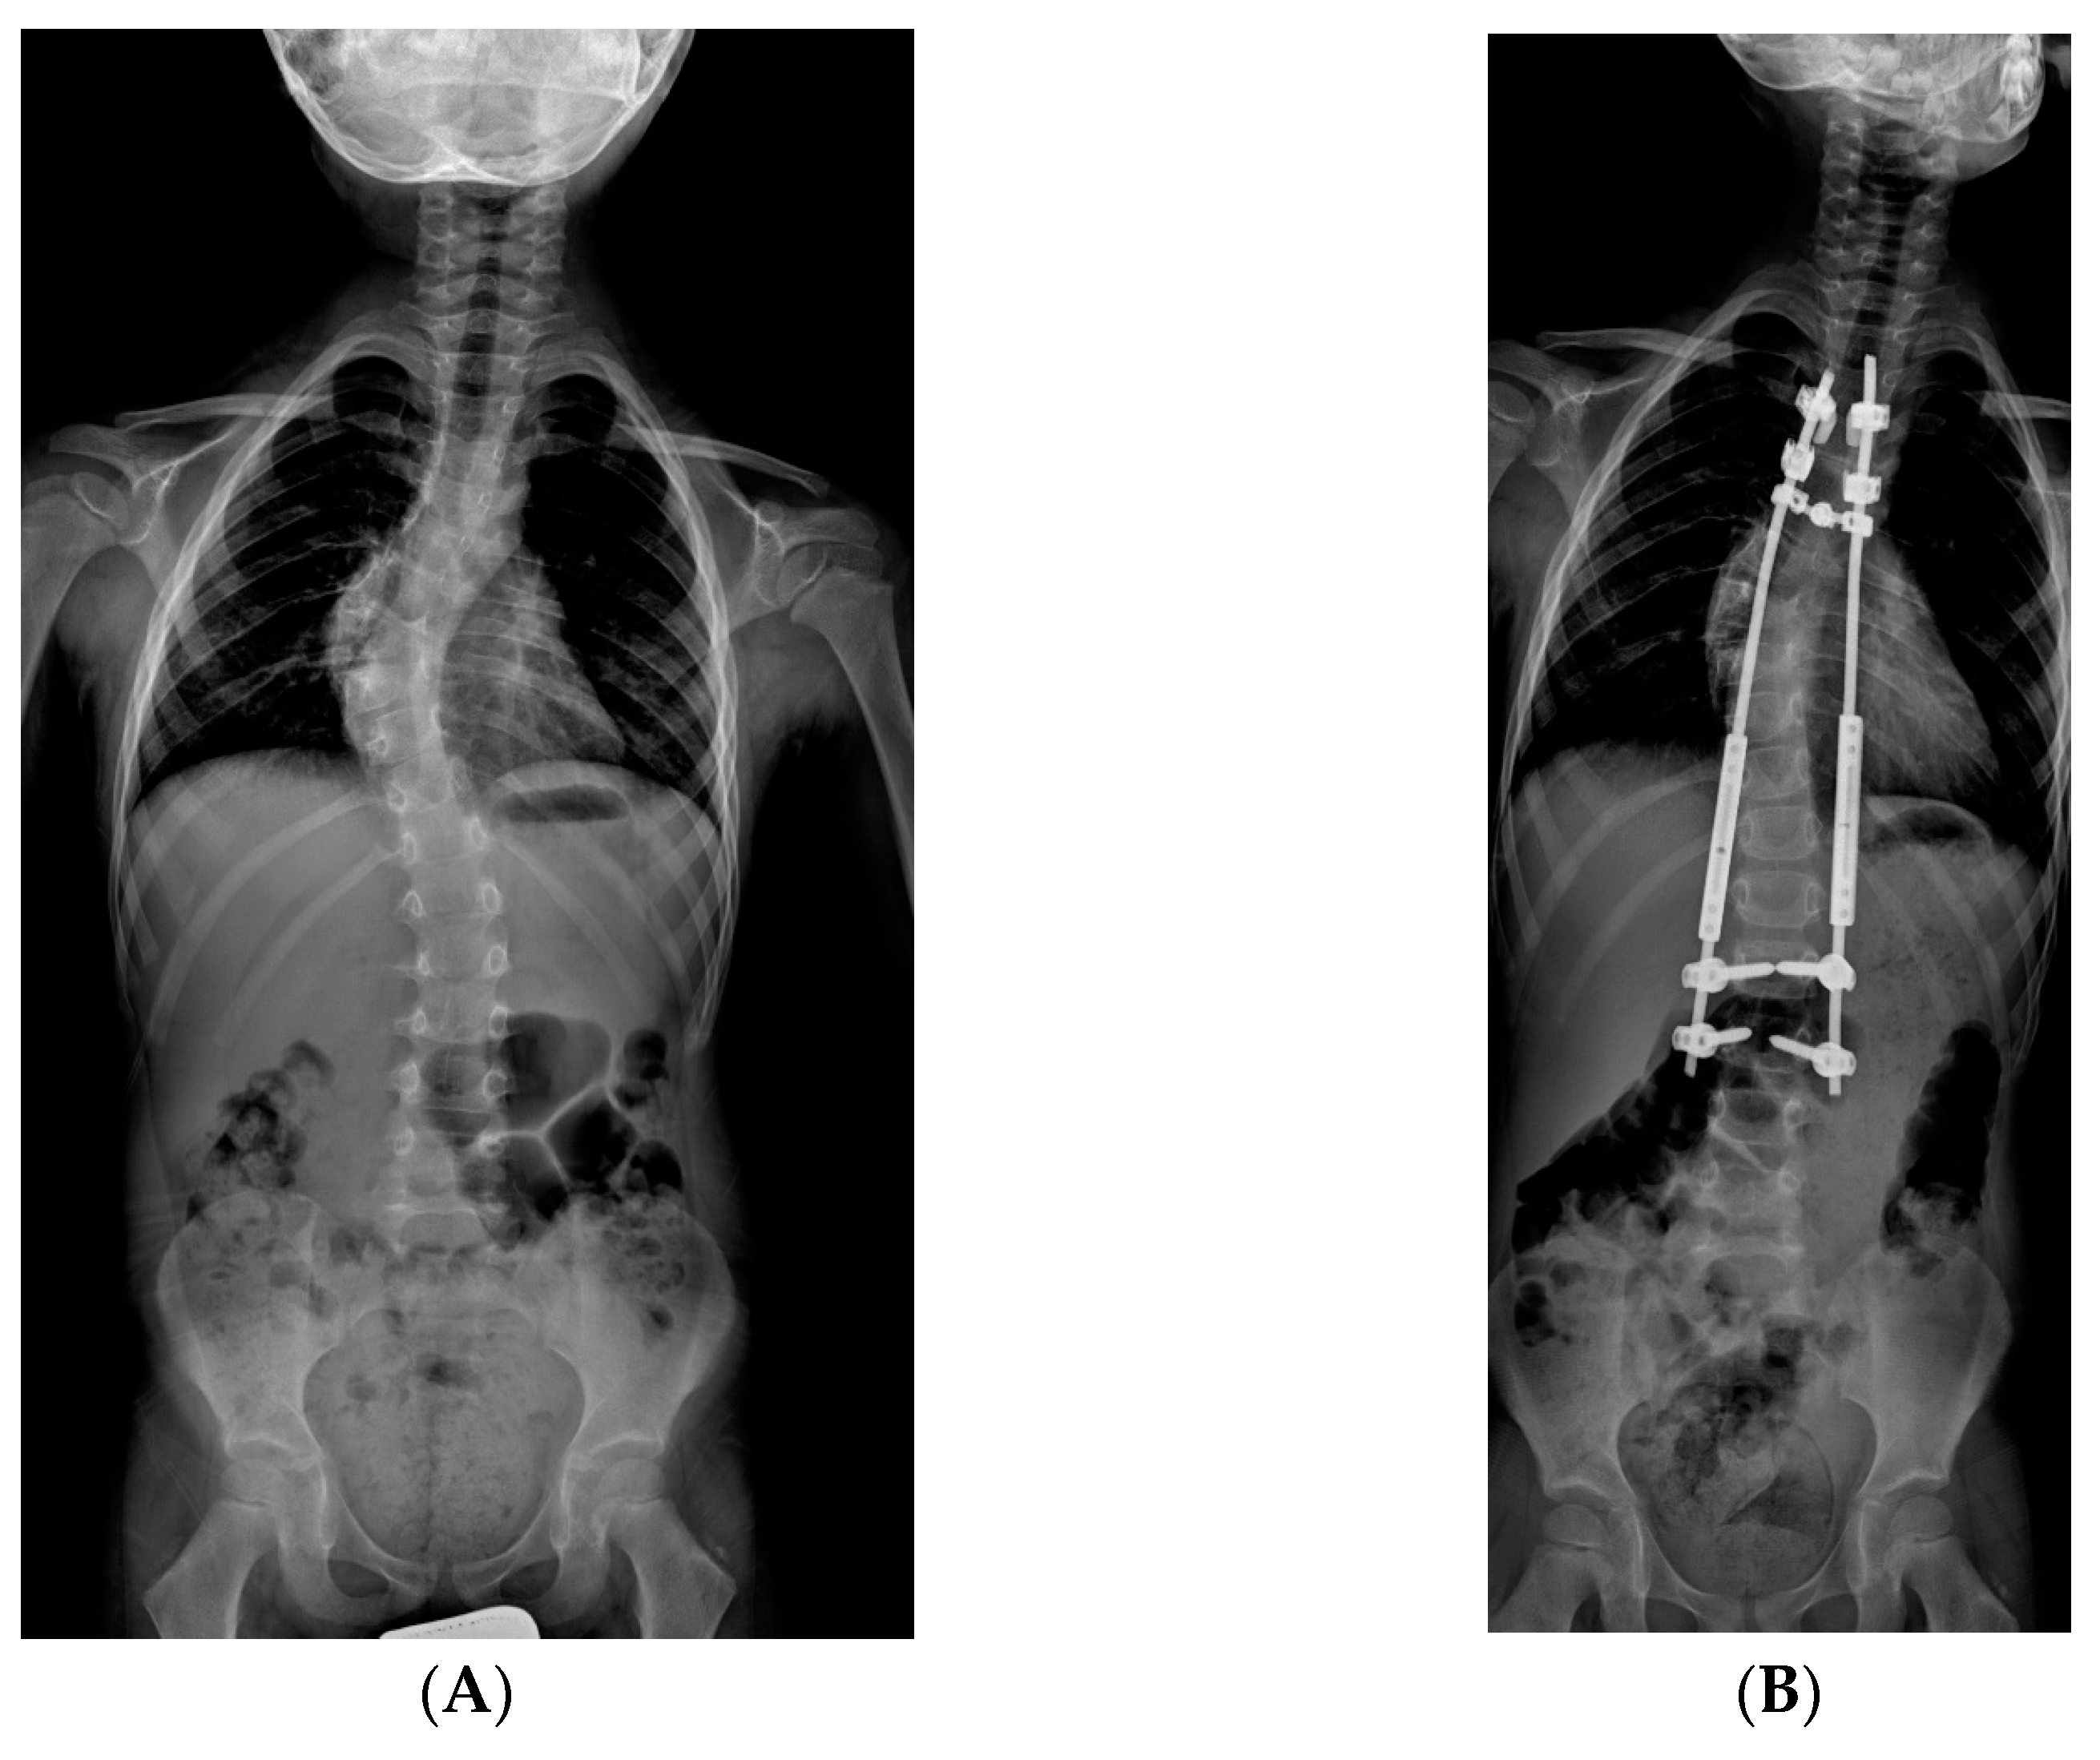

Figure 2.

X-rays of early onset scoliosis (EOS) corrected with traditional growing rods (TGR): (A) pre-operative antero-posterior X-ray view; (B) post-operative antero-posterior X-ray view; (C) pre-operative lateral X-ray view; (D) post-operative lateral X-ray view.

The TGR technique used in the examined cases consisted of a proximal and distal vertebral anchorage of two rods, each interrupted by a telescopic connector. Lengthening of the posterior structure was performed through a repetitive surgical procedure (on average every 8 months) involving distraction of the rods through the connectors. TGR was both a single rod implant, on the concavity side, and a dual rod implant. The dual rod construct, despite giving more stability, has the limitation of being bulky; for this reason it could not be performed in thin children or those of a very young age. In the TGR construct, both screws and hooks were used for proximal anchorage of the rods; screws were used for the distal one. The initial distraction was of moderate intensity in order to reduce the risk of vertebral anchorage failure and neurological complications.